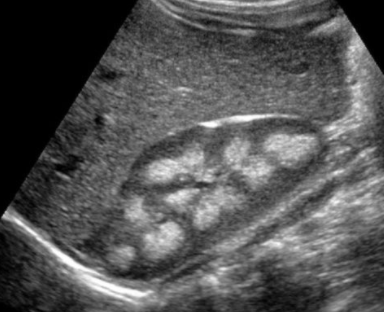

Néphrocalcinose corticale

- Sur chocs hypovolémiques (nécrose corticale aigue)

- Sur glomérulonéphrite chronique

- Sur Oxalose secondaire (anomalie du métabolisme de la bile sur problème du grêle (résections, Crohn))

- Sur Syndrome d’Alport

- Sur rejet de transplant rénal

Mnemotechnique GOAT - Glomerulonephritis - Oxalosis - Acute Cortical Necrosis - Transplantation